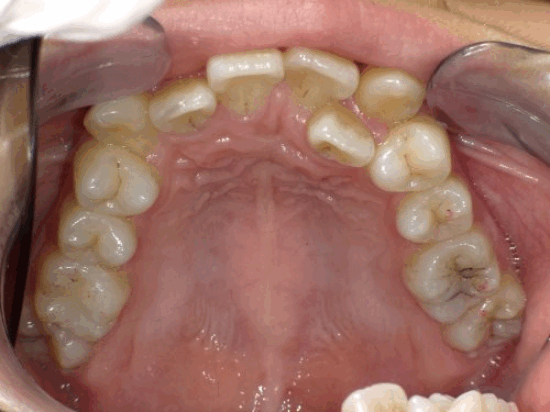

<症例7>歯がガタガタで噛み合わせが悪くお悩み

抜歯無し・マウスピースのみで矯正した症例です。

もともと歯列弓が非常に狭く、V字に近い形をしていたので噛み合わせも非常に不安定でした。

また、下顎前歯部がかなり上の方に生えていたため、下の前歯が上の前歯を突き上げてしまい出っ歯の状態になっていました。

現在では見た目はもちろん、臼歯の噛み合わせも改善しております。

奥歯の患者様も大喜びでした。

患者様と症状

主訴:歯のガタガタ、噛み合わせが悪い

性別・年齢:20代女性

問題点:叢生(重度)、V字歯列弓、ディープバイト

診断:前歯部の叢生を伴うアングルⅠ級、骨格性Ⅰ級の不正咬合

主なリスク:臼歯の移動に伴い一時的に咬合しにくくなる、歯肉退縮

症状:叢生(そうせい) 過蓋咬合(かがいこうごう)

治療内容

治療期間:1年10ヶ月

治療費用:990,000円(税込)

プラン:Full2プラン

抜歯:無し

再診治療費:無し

追加治療費:無し

保定装置費:無し

治療前後の写真